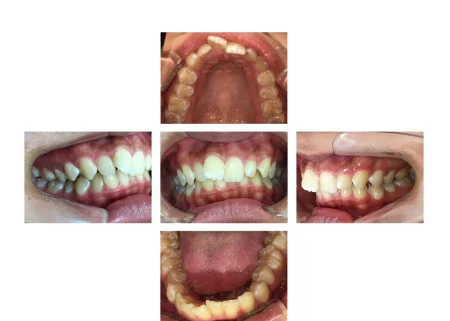

拝見したところ、歯並びの幅が狭くスペースが不足していることにより、歯がガタガタと並んでいる「叢生(そうせい)」でした。

特に上の前歯(右上中切歯/1番)は、ねじれて前方に突き出しており、見た目が気になりました。

また、上の歯が下の歯に覆い被さっている深い噛み合わせの「過蓋咬合(かがいこうごう)」も認められ、あごの関節に負担がかかりやすくなっていました。